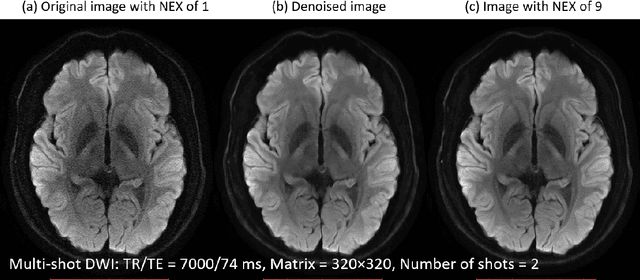

For several years, numerous attempts have been made to reduce noise and artifacts in MRI. Although there have been many successful methods to address these problems, practical implementation for clinical images is still challenging because of its complicated mechanism. Recently, deep learning received considerable attention, emerging as a machine learning approach in delivering robust MR image processing. The purpose here is therefore to explore further and review noise and artifact reduction using deep learning for MRI.